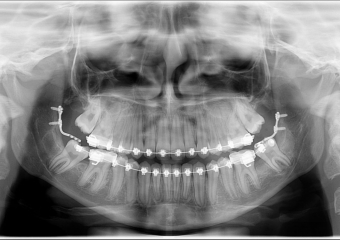

Rx Panorâmico Final, dentes totalmente posicionados e placas removidas - Clínica Cliniface

Rx Panorâmico Final, dentes totalmente posicionados e placas removidas